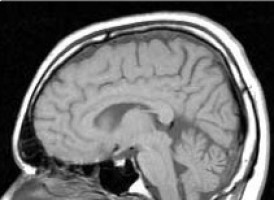

Uno de los tipos de cáncer más agresivos es el glioblastoma, una forma de tumor cerebral de muy mal pronóstico.